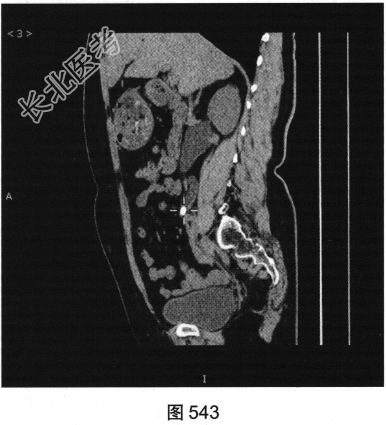

- 多项选择题3.[提示]CT平扫(图543、图544):约腰5椎体水平输尿管中段致密结节灶, 边界清楚,为0.8cm×0.5cm大小, 长轴平行于输尿管走行,边界清楚, CT值约735HU,局部输尿管管壁增厚、毛糙。应考虑的鉴别诊断为( )